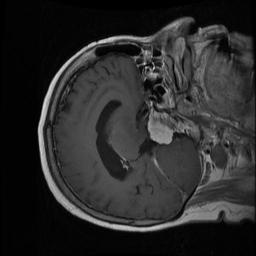

The dataset [19] contains 3064 T1-weighted contrast-enhanced images of the brains of 233 patients who had been diagnosed with one of three types of brain tumours: meningioma (708 slices), glioma (1426 slices), or pituitary tumour (930 slices). The information can be downloaded in the form of Matlab files (.mat files). Each image file includes a struct that contains pertinent information about the image, such as the label (1 for meningioma, 2 for glioma, and 3 for pituitary tumour), patient ID (PID), image data, and tumour Border. The tumor border is a vector that contains the coordinates of distinct points on the tumor’s edge, and it is obtained by manually tracing the tumor border. Due to the availability of this information, the generation of a binary image of the tumor mask is made simple. In addition, the dataset contains a tumor Mask, which is a binary image with the tumor region represented by a string of ones.

The distribution of the dataset is depicted in Fig. 4

Figure 4: The distribution of brain tumor dataset